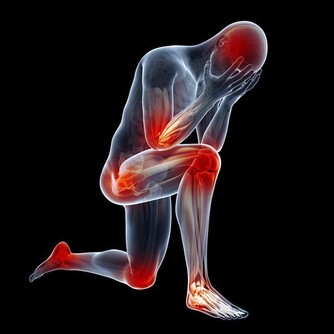

頭暈,發作時感覺天旋地轉,或者自覺旋轉不能站立,看不路面高低不平,有些人閉上眼睛可以緩解,有些人閉上眼睛也無法緩解。輕度頭暈一般都能控制,不會傾倒,對於嚴重頭暈的人,如若身旁沒有可以依靠或者手扶的東西,很有可能會傾倒,導致摔傷、碰傷,尤其是老年人,摔傷的後果很危險,甚至可能直接導致死亡。

很多疾病都會導致頭暈,如果你經常頭暈,要引起足夠的重視,及時查明病因,及早治療。導致頭暈的疾病大概有以下5種。

1、動脈狹窄

頸動脈硬化、腦動脈硬化,動脈管壁損傷,形成斑塊,導致管腔狹窄,血流不暢,影響腦供血,腦供血不足,腦組織得不到足夠的營養,就是出現頭暈的症狀,長期腦供血不足,腦組織會慢慢萎縮,影響智力,發展為血管性癡呆。

頸椎病主要是由於長期低頭或者外傷導致頸椎發生病變,包括頸椎骨質增生、椎間盤突出等等,導致椎管狹窄,也會導致椎動脈受到擠壓,椎動脈想腦部延伸,成為大腦供血主要干支,椎動脈狹窄,自然會使得腦組織缺血,也會產生頭暈。

3、腦梗塞

有腦梗賽病史的患者多有頭暈的臨床表現,頭暈表現為持續性,是腦血管梗阻後,相應區域內腦組織供血不足導致的。

4、血壓異常

高血壓患者血壓升高時會頭痛、頭暈,這是因為血壓升高後,腦部壓力也隨之升高,腦組織被擠壓,而有頭疼、頭暈。低血壓患者,血壓過低時也會出現頭暈症狀,主要是因為血壓過低,頭部位置高,血液運行不到頭部,造成腦供血不足所致。

5、低血糖

造成低血糖的原因主要有二個。一種是因為減肥,節食減肥,有些人為了減肥可以數天滴米不進,這樣做最直接的後果就是低血糖,有頭暈、乏力、出汗、心慌等等症狀,即刻補充糖分之後就快速緩解。

另一種原因是高血糖,與低血糖恰恰相反。血糖高的人為了控制自己的血糖到理想的狀態,加大降糖藥的用量,不科學控制飲食,是低血糖的常見誘因,低血糖時,腦部處於低糖狀態,能量供給不足而頭暈,低血糖嚴重時可以導致休克。

通過上面的描述,大家大概可以了解平時有頭暈症狀,可能是得了什麼病。

這些疾病都會對身體產生不可恢復的不良影響,所以平時經常頭暈,或者頭暈發作頻率逐漸增加,越來越嚴重,一定要及時去醫院就診,明確病因,對症治療。